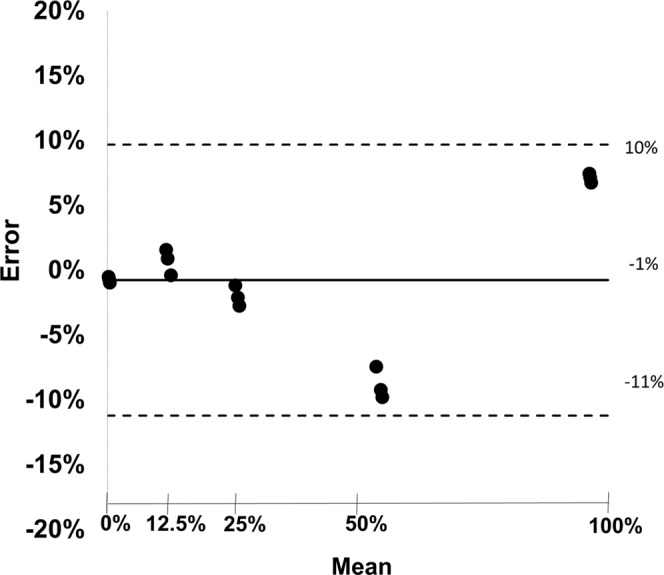

Figure 3 shows a calibration curve of the tantalum material. With its aid, additional scans were analyzed and tantalum dilution concentrations were calculated. The quantitative measurements of the tubes with different tantalum concentrations matched well with the actually known mixtures (measured: 92.92 ± 0.004%, expected: 100%; measured: 58.85 ± 0.01%, expected: 50%; measured: 27.03 ± 0.01%, expected: 25%; measured: 11.84 ± 0.01%, expected 12.5%; measured: 0.73 ± 0.002%, expected: 0%; RMSE = 0.05). A corresponding Bland-Altman plot is displayed in Fig. 4, highlighting the difference between measured and expected tantalum concentrations versus the average of measured and expected tantalum concentrations. All measurements are located within the range of confidence limits (1.96).

Figure 4.

Bland-Altman plot showing difference between measured and expected tantalum concentrations versus average of true and expected tantalum concentrations. The black line represents the bias and the dashed lines represent upper and lower limits of the mean (confidence limits ± 1.96).